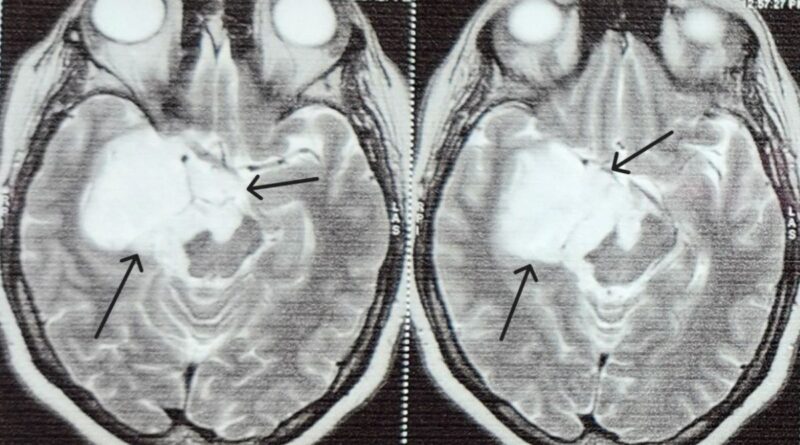

After an epidermoid tumor was found underneath a 45-year-old dessert chef’s brain through Magnetic resonance imaging who had recurrent seizures sought assistance from Dr. L H Hiranandani Hospital. The tumor had enveloped important nerves that help in vision and eye movement causing serious impairment of her sight and increasing the number of seizures.

Epidermoid tumors are non- cancerous, usually slow-growing masses occurring as a result of errors in cell migration during embryonic stage of development. These tumours contain a thick yellow substance called keratin and may compress neighboring areas of the brain leading to severe neurological symptoms.